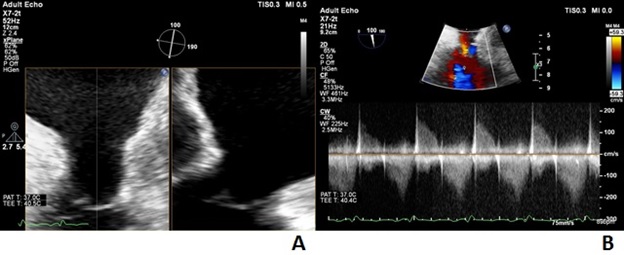

Subsequent work-up included an abdominal ultrasound that showed hepatic congestion and cirrhosis. A cardiac magnetic resonance imaging (MRI) showed tricuspid stenosis, likely due to dysplastic tricuspid valve leaflets that appeared thickened without significant TR. The tricuspid valve annulus measured 24 mm in transverse diameter and 23 x 32 mm in short axis. The tricuspid valve annulus area was 5.5 cm2. A transesophageal echocardiogram confirmed a narrow, hypoplastic, dysplastic, and lipomatous tricuspid annulus measuring 1.7 x 2.1 cm at the base of the tricuspid leaflets (Figure 1A). There appeared to be commissural fusion and restriction of the leaflet tips with a peak gradient of 18 mm Hg and a mean of 10 mm Hg at a heart rate of 86 bpm (Figure 1B). Finally, after a trial of diuretic therapy, diagnostic cardiac catheterization still showed a mean right atrial pressure of 21 mm Hg and a right ventricular pressure of 31/7 mm Hg with a mean diastolic tricuspid valve gradient of 11 mm Hg at 78 bpm. Her case was discussed at our multidisciplinary adult congenital heart disease (ACHD) conference; the consensus was that, given her peripheral edema, liver congestion, and cirrhosis, she should undergo an intervention with PTBV as the first line.

Under conscious sedation, access was obtained in the right femoral vein with an 8 French (Fr) sheath and in the right femoral artery with a 5 Fr sheath. The patient received 2 g of Cefazolin and 10 000 units of unfractionated heparin intravenously, achieving an activated clotting time of 292 seconds. A 7 Fr balloon wedge catheter (Teleflex Medical) was used to exchange for a soft J-tip exchange length wire. We then placed a Langston 6 Fr dual-lumen pigtail catheter (Vascular Solutions) to take simultaneous gradients across the tricuspid valve. The mean diastolic gradient was 10 mm Hg with a right atrial mean pressure of 25 mm Hg (Figure 2A). A modified Safari Extra Small wire (Boston Scientific) was then introduced in the right ventricle, and a 34-mm AGA sizing balloon (AGA Medical Corporation) was placed across the TV. Upon inflation, we only noted a waist at the level of the leaflet tips measuring 15 mm on a calibrated measurement. Though the balloon was inflated up to 24 mm proximally, the annulus could not be delineated (Figure 3A).

Given this and the TEE measurements, we decided to start with a 20 mm x 5-cm Z-Med II-X balloon (B. Braun Interventional Systems). Using a hand inflation estimated at less than 2 atmospheres twice (10 seconds each), the waist dilated easily. The balloon was removed, and both echocardiographic and hemodynamic assessments were performed. The right atrial mean pressure dropped to 23 mm Hg, and the mean diastolic gradient across the TV was 7 mm Hg by both modalities (Figure 2B). There was no significant regurgitation. We then introduced a 22 mm x 5-cm Z-Med II-X balloon (B. Braun Interventional Systems) and dilated it again at a similar pressure twice (10 seconds each). Post-inflation assessments showed a right atrial mean pressure of 24 mm Hg with a mean diastolic gradient of 6 mm Hg by cath and 5 mm Hg by transthoracic echocardiogram (TTE) (Figure 2C). There was trivial regurgitation. We then repositioned the sizing balloon within the valve annulus. On inflation, the valve leaflet tip opening was 20 mm, as was the annulus (Figure 3B).